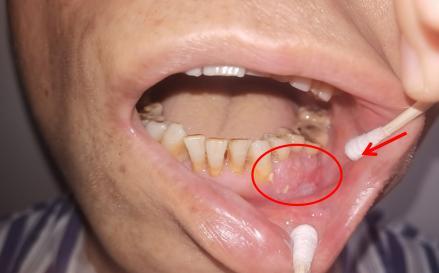

李先生因发现左侧下颌牙龈长有肿物,来到益阳市中心医院口腔科门诊就诊,切取活检样本后,病理结果显示为左侧下颌牙龈高分化鳞癌。患者随即入住口腔科病房,在完善相关检查后,发现左侧颈部淋巴结肿大,考虑淋巴结转移可能。

(▲患者左下颌牙龈肿瘤)